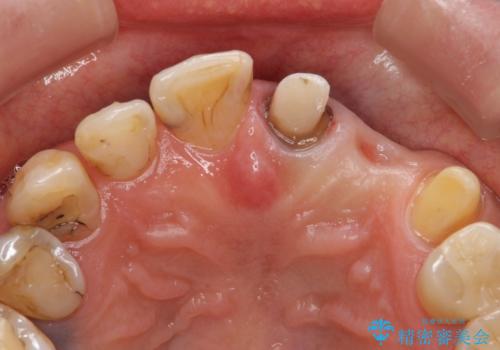

左上1、2番目の歯は仮歯の状態だったので外して状態を確認したところ、左上2は垂直的な歯根破折を認めたため抜歯となりました。左上1は再根管治療を行いました。

左上2抜歯後、骨および歯肉の回復を待ち、オールセラミッククラウンのブリッジによる欠損補綴を行いました。